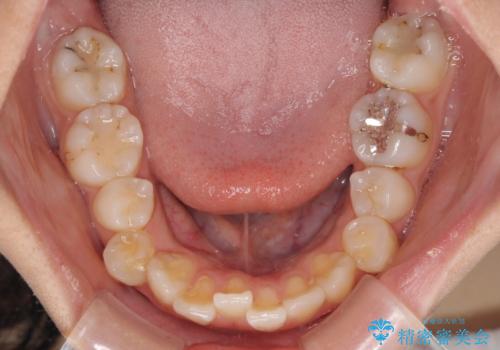

- 下顎の前突感と前歯の叢生を気にして来院された患者様です。

急速拡大装置を用いて上顎骨を側方に拡大し、上顎の叢生を解消するとともに下顎歯列拡大により下顎の叢生も解消することとしました。